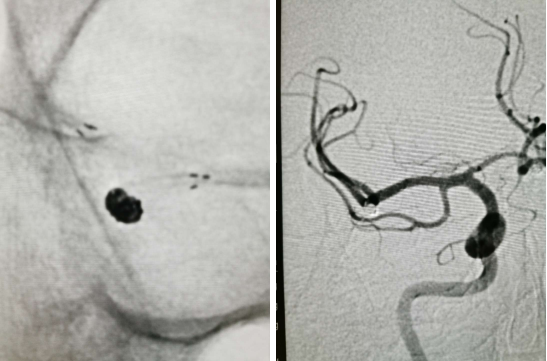

外院CTA2020.9.19

外院DSA

右颈动脉

左椎动脉

左颈动脉

诊断:右侧前交通动脉瘤

患者在全麻下、多参数监护仪监测下行前交通动脉瘤经右侧颈内动脉支架辅助下栓塞术。全麻后,常规消毒销巾,采用改良seldinger技术穿刺右侧股动脉或功,置入6F动脉鞘。黑泥鳅导丝及多功能导管带领6F MPD导管达到右侧颈内动脉岩段,行造影见∶前交通动脉瘤,瘤体3.5 mm*5.1 mm。在路图引导下,徵导丝(Synchro 0.014 in*200 cm)带领弹支架微导管(SL-10)到右侧大脑前动脉A2段,退出微导丝。微导丝(Synchro 0.014 in*200 cm)带领弹簧圈微导管(eV3 Echelon-10)到达前交通动脉瘤体内,退出微导丝。经弹簧圈微导管填入首枚弹簧圈(Codman COMPLEX XTRASOFT3 mm*6 cm)成篮良好,在路图引导下在支架管内输送支架(Neuroform Atlas 3.0 mm*21 mm)并释放完全覆盖动脉瘤颈,造影可见支架打开良好解脱首枚弹备圈,沿弹簧圈导管继续填入弹簧圈(可见护理记录单)间断造影确保双侧大脑前动脉血流通畅。右侧颈内动脉造影确认∶前交通动脉瘤填塞致密,双侧大应前动脉血流通畅。手术结束。右侧股动脉鞘处用血管封堵器(Coxrds Exoseal 6F)封堵,并压迫器持续压迫。木后患者清醒。